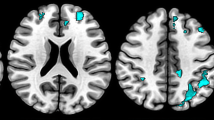

In HC group, the DN positively connected with the bilateral cerebellar anterior and posterior lobes, the bilateral thalamus, the bilateral striatum (putamen and caudate), the bilateral globus pallidus and the brainstem; and negatively connected with the bilateral prefrontal cortex, the bilateral middle occipital lobe and the bilateral inferior parietal lobule (Fig. 2).

Brain regions that functionally connected with the bilateral DN in HC, TD and NTD groups. The statistical significant level was set at p < 0.05 and cluster size >5400 mm3. Cool color represents negative correlation and warm color represents positive correlation. The left side of the image corresponds to the right side of the brain in axial orientation; Slice coordinates according to MNI space are shown in the upper right corner of the slices, indicating Z axis in axial orientation

In TD and NTD groups, DN functional connectivity showed similar pattern with HC group in the bilateral cerebellar anterior and posterior lobes, the bilateral thalamus, the bilateral globus pallidus, the bilateral inferior parietal lobule and the bilateral middle occipital lobe. In addition, DN had scarce functional connectivity with the putamen and caudate in TD and NTD groups (Fig. 2).